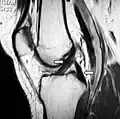

The posterior cruciate ligament (PCL) is a ligament in each knee of humans and various other animals. It works as a counterpart to the anterior cruciate ligament (ACL). It connects the posterior intercondylar area of the tibia to the medial condyle of the femur. This configuration allows the PCL to resist forces pushing the tibia posteriorly relative to the femur.

The PCL is located within the knee joint where it stabilizes the articulating bones, particularly the femur and the tibia, during movement. It originates from the lateral edge of the medial femoral condyle and the roof of the intercondyle notch[2] then stretches, at a posterior and lateral angle, toward the posterior of the tibia just below its articular surface.[3][4][5][6]